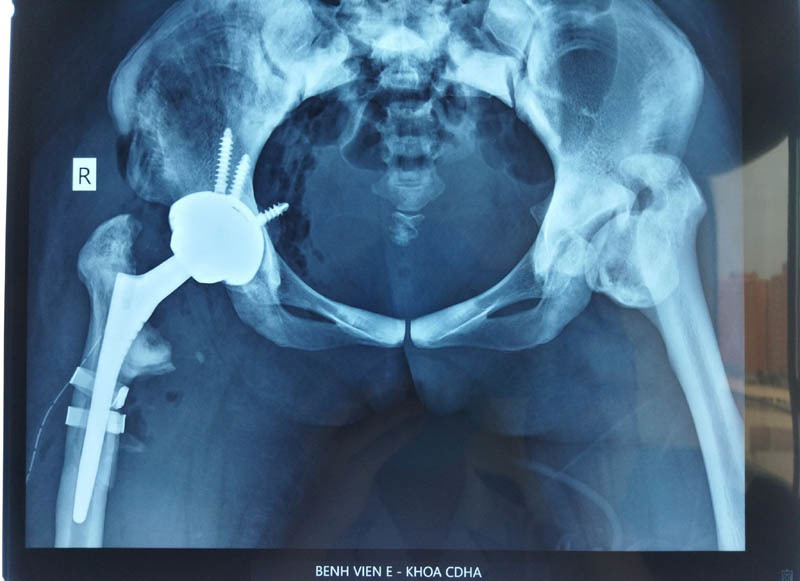

| Phim Xquang của bệnh nhân sau mổ |

9h sáng ngày 26/10, bệnh nhân được gây mê. Quá trình mổ diễn ra đầy khó khăn như các bác sĩ dữ liệu. “Mặc dù kéo giãn nhưng chi bệnh nhân vẫn co rất nhiều, chảy máu khá nhiều. Đặc biệt, quá trình cưa cổ xương đùi cũ của bệnh nhân cũng rất khó khăn. Mật độ xương đặc, mặc dù dự trù các lưỡi cưa sắc nhất, mới nhất nhưng vẫn bị hỏng cưa. Chúng tôi phải thay lưỡi cưa mới”, BS Hiếu nói thêm.

Đến bước làm sạch ổ cối để đặt ổ cối nhân tạo cũng là một khó khăn nữa vì ổ cối của bệnh nhân nông, phải tạo hình lại dẫn đến kéo dài thời gian ca phẫu thuật.

Quá trình phẫu thuật, 1 trong 2 thành xương bị gãy. Đây là điều không quá bất ngờ, vì ekip phẫu thuật đã xác định từ trước. Sau khi đặt xong chuôi khớp trong ống tủy xương đùi, dùng dụng cụ cố định lại phần xương gãy, đặt lại khớp, cuộc phẫu thuật mới kết thúc khi kim đồng hồ vượt quá 12h30.

“Cải thiện nhìn thấy rõ là 2 chân bằng nhau, thậm chí chân mổ dài hơn một chút. Khớp háng bên kia của bệnh nhân cũng hỏng, dự kiến sẽ phải mổ tiếp, như vậy 2 chân bệnh nhân mới có thể bằng nhau”.